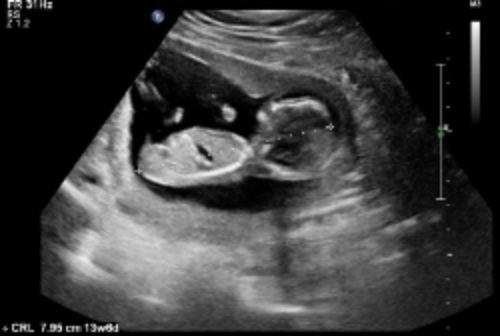

Here are some u/s pics from my friend at 13 weeks. Any nub guesses?

Attachment 24162

If the third pic has the nub (not an expert, so could be something else) I'd say boy!